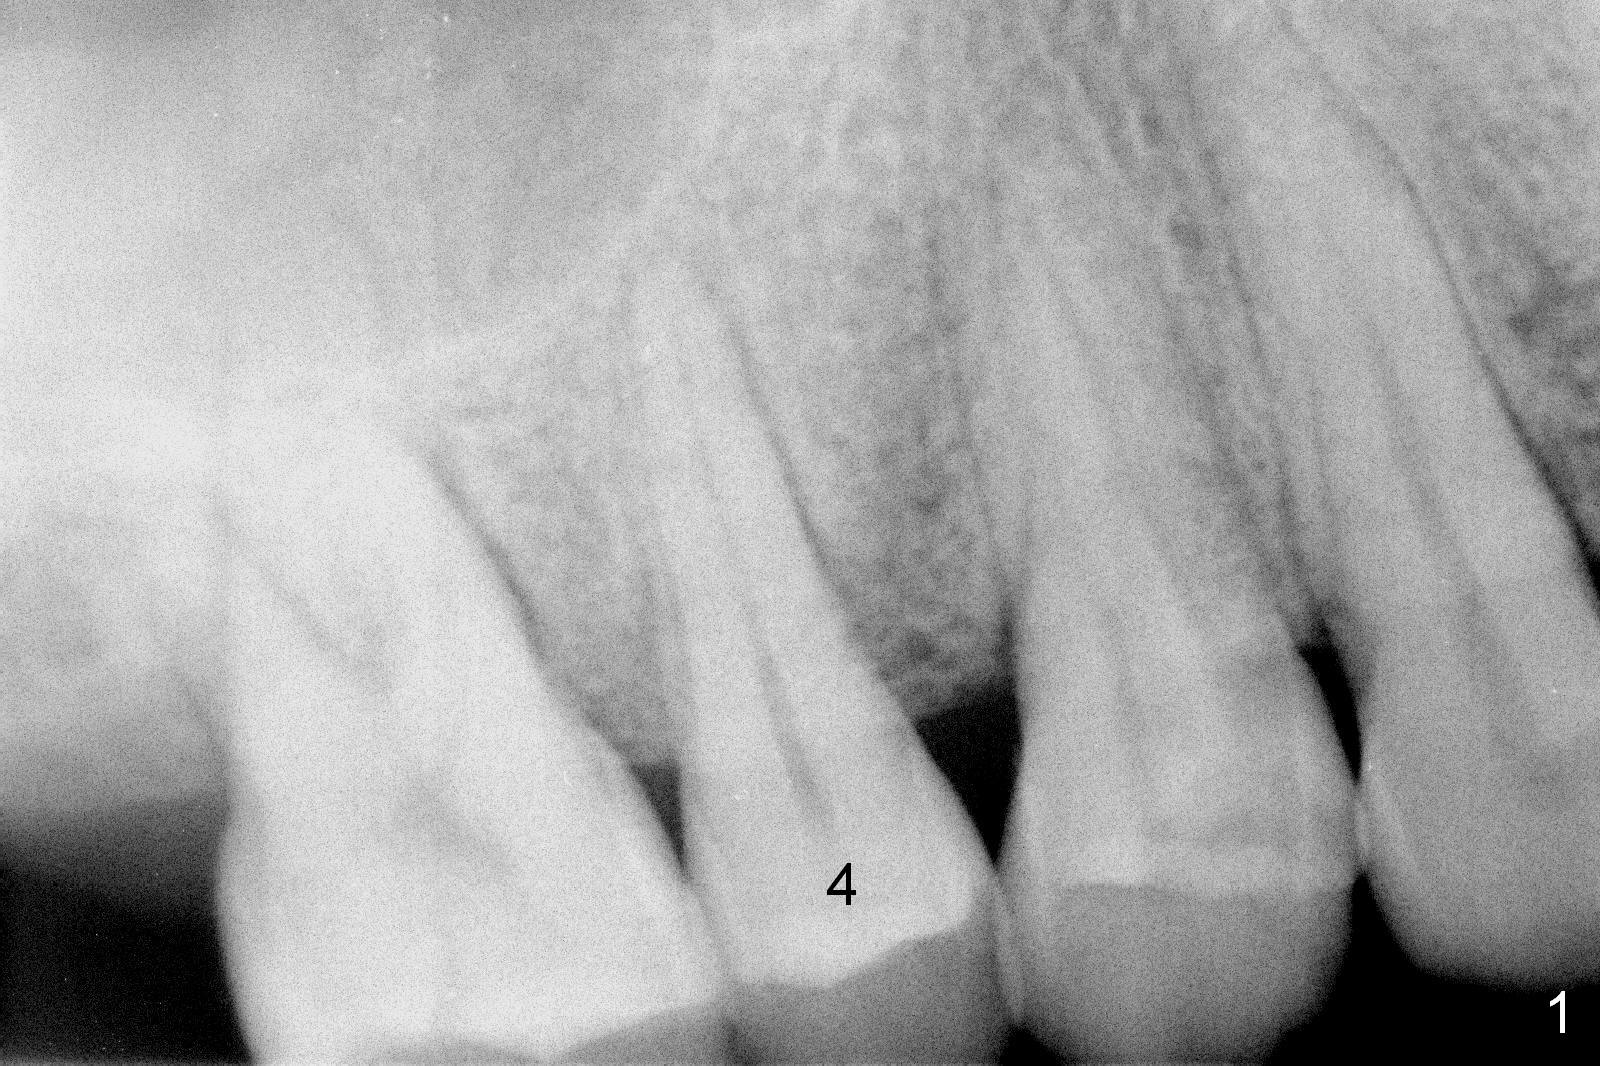

A 47-year-old man returns emergently with subgingival fracture of the lingual (L) cusp of the tooth #4 (Fig.1-3).  After extraction (no bony defect) without drilling, a 4x11 mm dummy implant is placed as a tap drill with satisfactory stability (Fig.4,5).  To get subcrestal placement, a shorter (4x9 mm) implant is inserted with insertion torque of < 35 Ncm.  In retrospect, a larger implant (4.5 mm) would be better in term of primary stability.  After allograft placement into the buccal and lingual gaps, a 4.5x4(4) mm abutment is placed for an immediate provisional.  There is a peri-implant gap 7 months postop (Fig.7<, as compared to the implant at #2 (6 months postop)) .  When the loose abutment is being retightened, the patient feels pain, although the gingiva appears healthy (Fig.8).  A larger implant should have been used; the abutment should have been removed.  The implant dislodges while the abutment is untightened 8 months postop.  The osteotomy is found intact.  A 4.5x11 mm dummy implant is placed 2 mm subgingival with 20 Ncm (Fig.9).  When a 4.5x11 mm definitive implant is placed 3 mm subgingival (Fig.10,11), torque reaches 50 Ncm.  A 5.5x3 mm healing abutment is placed.  Three months postop, the implant is stable (Fig.12,13) and impression is taken.